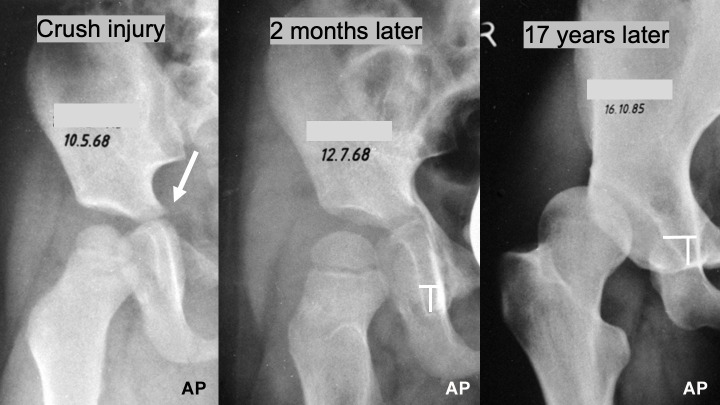

Aims: The Bernese periacetabular osteotomy (PAO) is typically not performed until after the growth plates have closed in late adolescence, as the osteotomy crosses the posterior branch of the triradiate cartilage, which could potentially cause deformities similar to post-traumatic dysplasia, a condition observed following pelvic fractures in childhood. The aim of this study was to retrospectively analyze on radiographs whether the PAO, when performed in children with open growth plates, affects acetabular development.